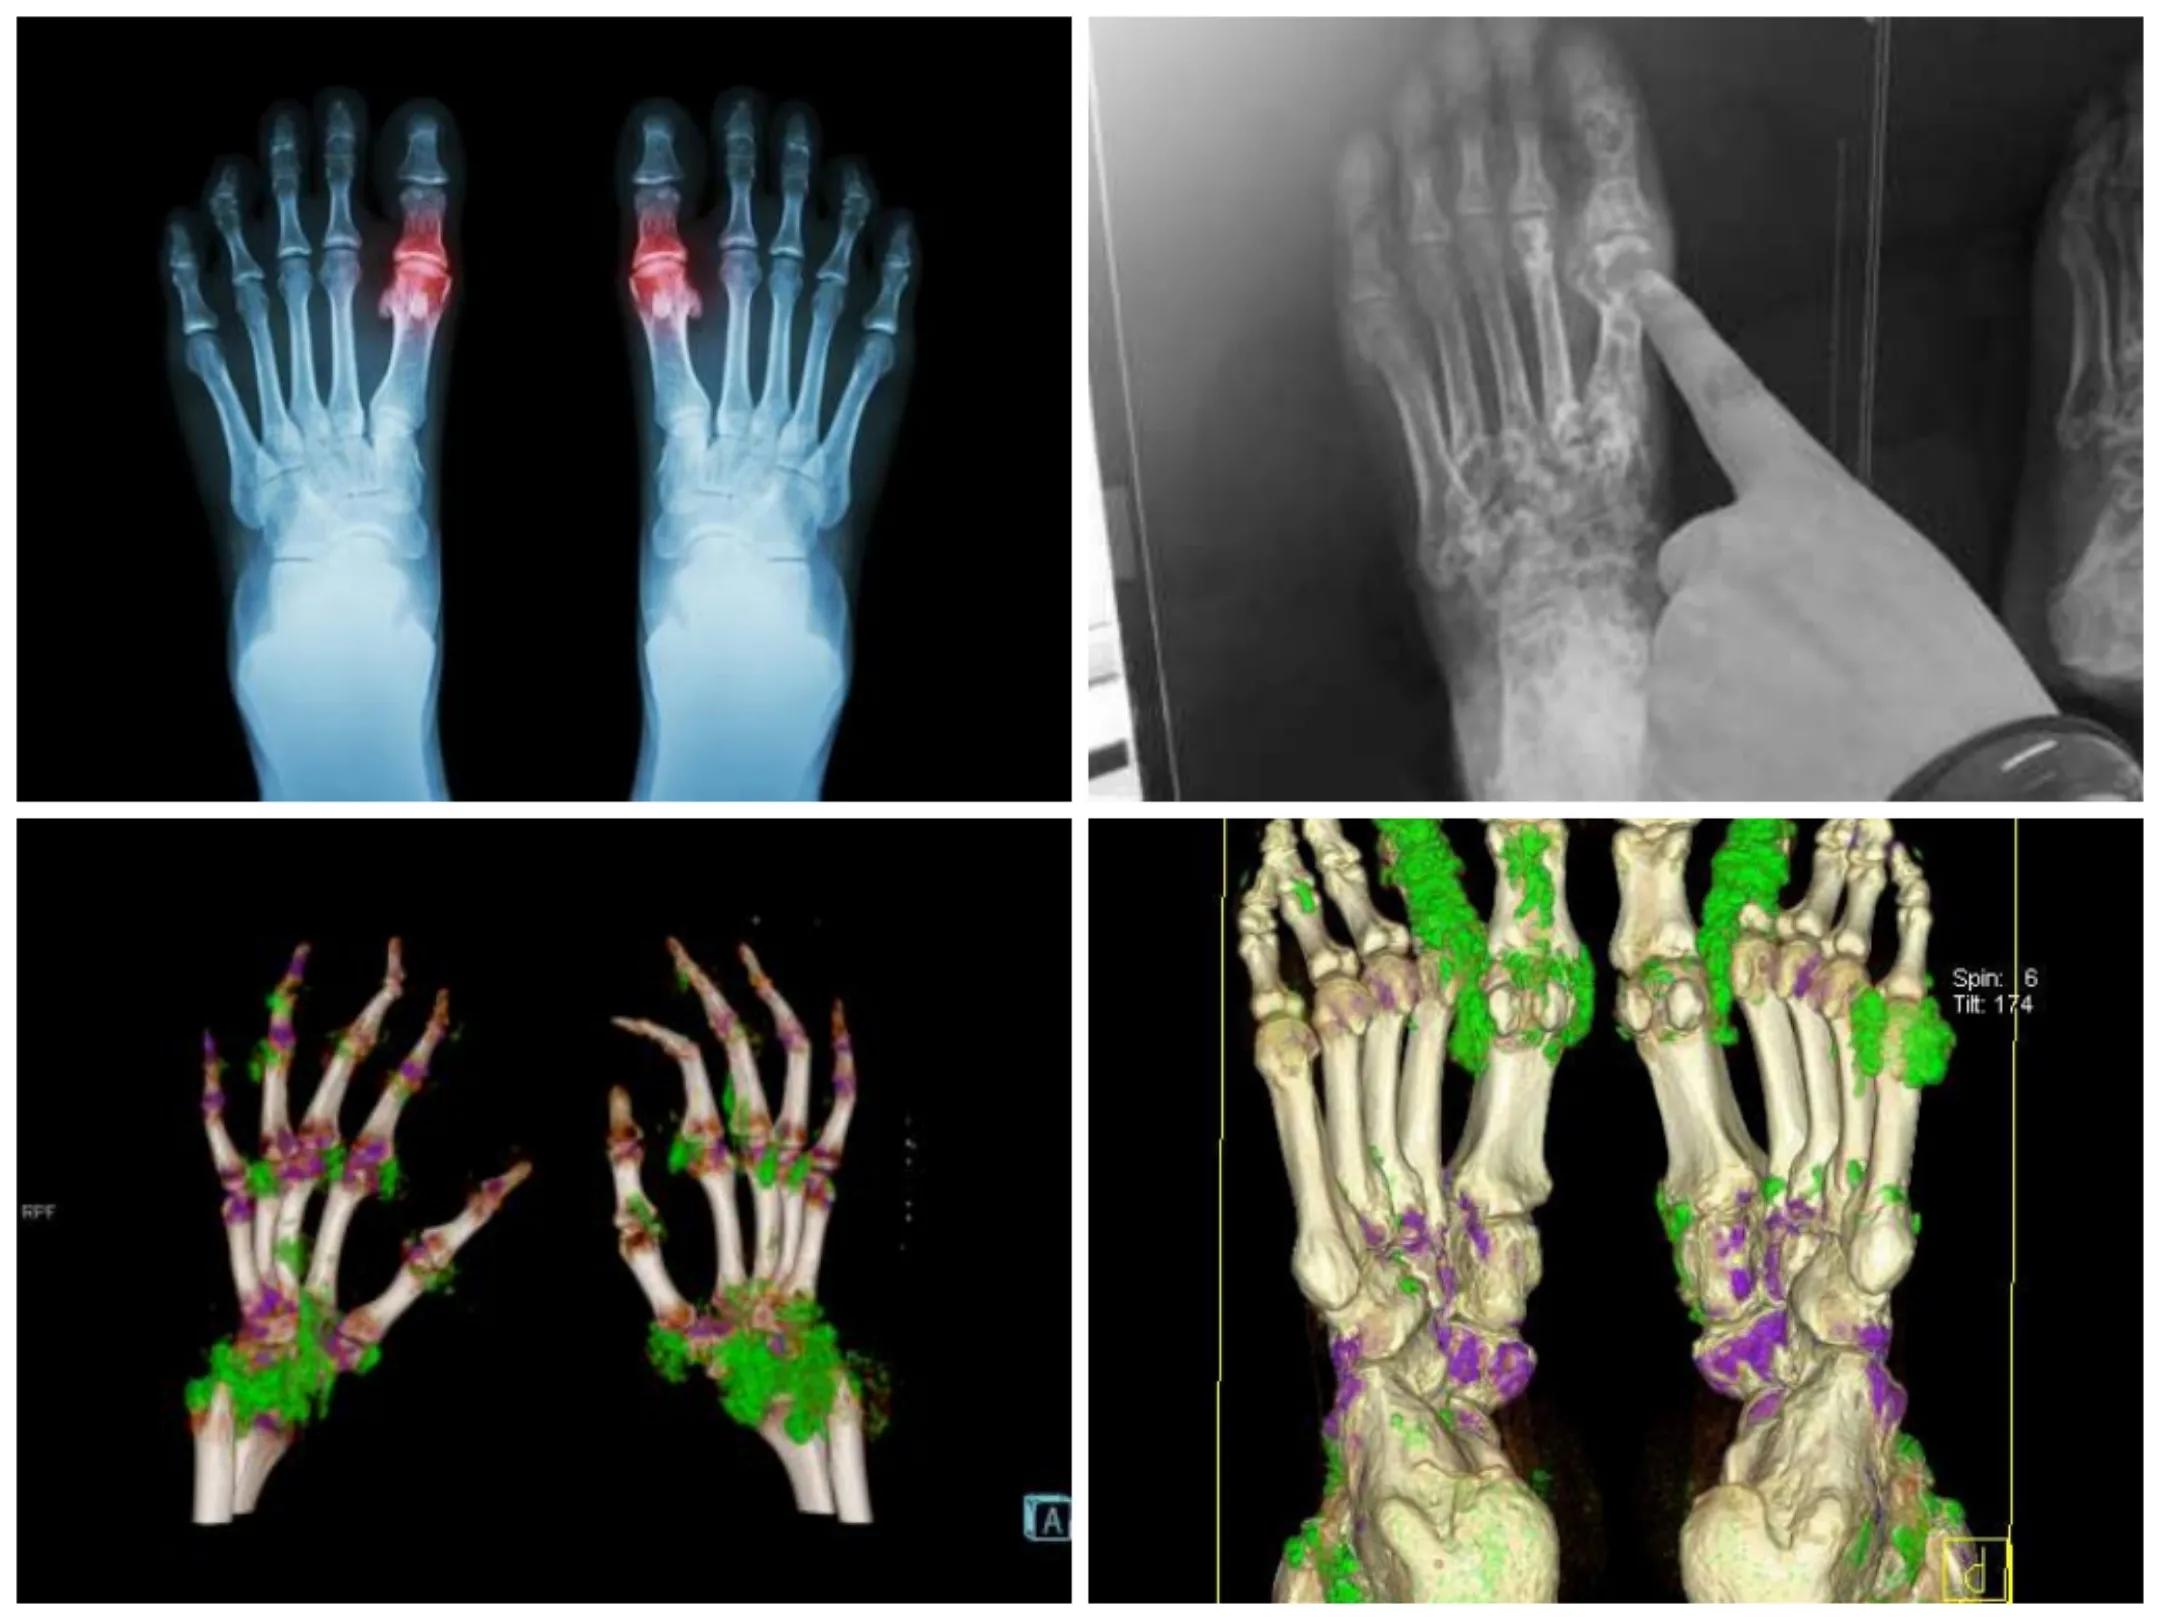

痛风是由于人体内血尿酸过度升高导致的一部分尿酸盐沉积在人体关节及皮肤结缔组织形成大小不一的尿酸盐结晶,造成关节红肿热痛的症侯群,影响关节功能。痛风石常见于耳轮、拇趾关节,其它关节少见,很少侵蚀大关节。高尿酸血症是痛风发生的关键和基础,也就是说痛风是以高尿酸血症为前提的。5--10%的高尿酸患者有痛风发作,多在饮酒、高嘌呤饮食、劳累、受凉、负性情绪、剧烈的运动、手术、外伤骨折、感染、药物等诱因下出现急性发作、单一、非对称的关节疼痛肿胀,以第一跖趾关节多见,数日可自行缓解,间歇期正常。严重时影响活动。痛风性关节炎反复发作可影响关节功能、导致大关节受累、逐渐发展为关节积液,并逐渐导致关节畸形。

慢性痛风期:痛风石的形成是痛风进入慢性期的表现。痛风石为尿酸盐反复沉积被细胞及组织包围、增生形成的产物。常见于关节内及其附近。典型部位是耳廓、手指、足趾、足跟、膝、腕、肘等。发生于关节内的痛风石可导致关节肿痛、破坏、畸形、强直甚至骨折。有时需手术治疗。关节内穿刺和注射长效激素对治疗急性痛风是有效和安全的。

痛风的诊断很简单,根据临床症状、血尿酸水平、关节液及组织学尿酸盐结晶检查及影像学改变拍X光片、双能CT等就可明确诊断。